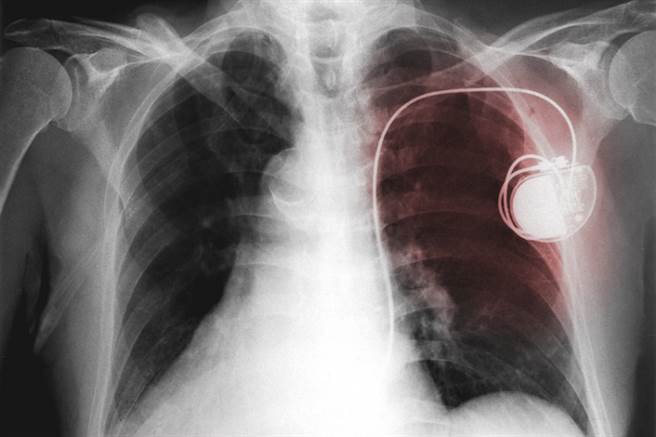

正常成人的心跳速率每分钟在60~100次之间,心臟跳动是有规律的,并随着身体状况加快或减慢,正常人不会感觉或意识到心臟在跳动。而 「心律不整」指的是心臟节律不正常,心跳不规则、过快或过慢。心律调节器是一种植入在体内的人工装置,当心臟跳动太慢时,可以刺激心臟,让它能按照适当的速率持续跳动。

心跳太慢者严重会猝死,若是症状影响到日常生活,医师建议考虑装置心律调节器。(图/常春月刊提供)

心律调节器是一个人工电池,由节律器(pulse generator)、电极(electrode)及导线(lead)三部 分所组成,扮演的角色就像指挥官,能代替心臟的窦房结来发号施令,使心臟规律地跳动起来。

吴孟修解释,手术过程很简单,经过局部麻醉后,在锁骨下方切个3公分的小伤口,将导线经由锁骨下的静脉放入心房或心室中,再把导线前端 的电极固定在心房或心室的心内膜,而后把人工心臟节律器植入胸部上方的皮肤下层就能完成手术,通常手术时间约1~2小时。